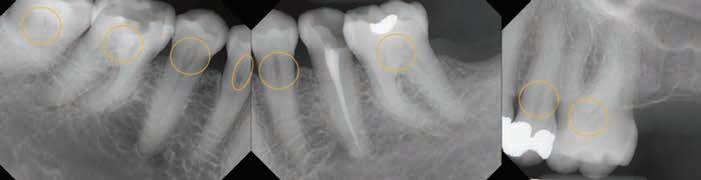

Her full mouth intraoral radiographs revealed generalized pulpal calcifications of various dimensions in the pulp chambers and root canals. In at least one tooth, multiple discrete pulpal calcifications were observed. All teeth with existing pulpal calcifications were asymptomatic, and did not show any radiographic signs of periapical bone loss or periodontal ligament (PDL) widening.

Figure 1. Full mouth radiographic survey reveals multiple pulpal calcifications of various dimensions affecting the pulp chamber and radicular pulp of patient’s remaining dentition.

Figure 2. Full mouth radiographic survey reveals multiple pulpal calcifications of various dimensions affecting the pulp chamber and radicular pulp of patient’s remaining dentition. Multiple discrete pulpal calcifications can be noted on upper left first molar pulp chamber.